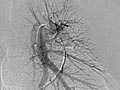

Angiogram of the Lung

An angiogram of the lung is an X-ray test that uses a special dye and camera (fluoroscopy) to take pictures of the blood flow in the blood vessels of the lung.

A lung (pulmonary) angiogram is used to check the arteries that lead to the lungs (pulmonary arteries) and the blood vessels in the lungs. It can also find narrowing or a blockage in a blood vessel that slows or stops blood flow.